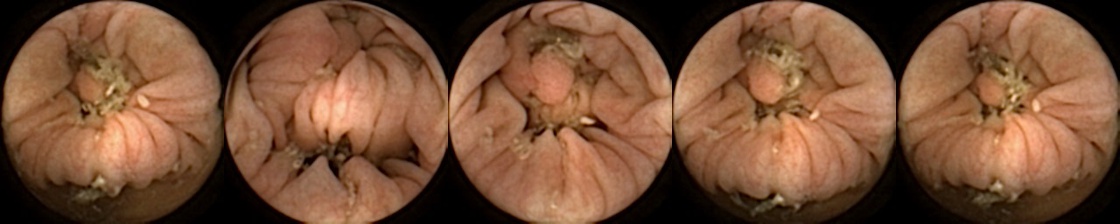

Figure 3 shows classification output examples for the MIV model using the pretrained ConvNext. Note that the model has a test accuracy of 83.66% for DBA L2 with 2 heads. In each row, the leftmost image is the query and the four images to the right of each query are the target images. The True Positive (left-top) and True Negative (bottom-right) examples outline the cases when the model is able to successfully distinguishes images containing unique polyps from those with dissimilar polyps. The False Negative (top-right) and False Positive (bottom-left) examples show the cases where the model fails to correctly distinguish images of unique polyps and images of dissimilar polyps. Further, we can note from the differences in the examples of True Positives and False Negatives that when the query image and the target set instances differ from each other in some ways, then the model can misclassify images. These differences could be attributed to different views due to the dynamics of the camera inside the colon, different views from two camera heads of the capsule, or presence of artifacts such as bubbles, debris, and small bowel secretions.

Similarly, we consider examples for the MIV model based on SimCLR pretraining using the pretrained ConvNext backbone in Figure 4. The model has a test accuracy of 86.26% for DBA L1 with 2 heads. Here we note again a similar trend by looking at the True Positive and False Negative examples as observed before, where a significant difference in the query image when compared with the target images can lead to a failure to identify the same polyp images in the five examples. A look at the False Positive examples affirms that the task remains challenging, as evidenced by the model’s occasional misclassifications in ambiguous cases.

We can additionally consider the confusion matrices from the best MIV model associated with (a) the pretrained ConvNext and (b) SimCLR pretraining using the ConvNext backbone in Figure 5. We note that using SimCLR achieves a better ratio of False Negatives (70) to False Positives (38) as compared to pretrained ConvNext, which has 109 False Negatives and 23 False Positives.

Refer to caption

Figure 5: Confusion matrices from the best MIV model associated with (left) the pretrained ConvNext, and (right) SimCLR pretraining using the ConvNext backbone